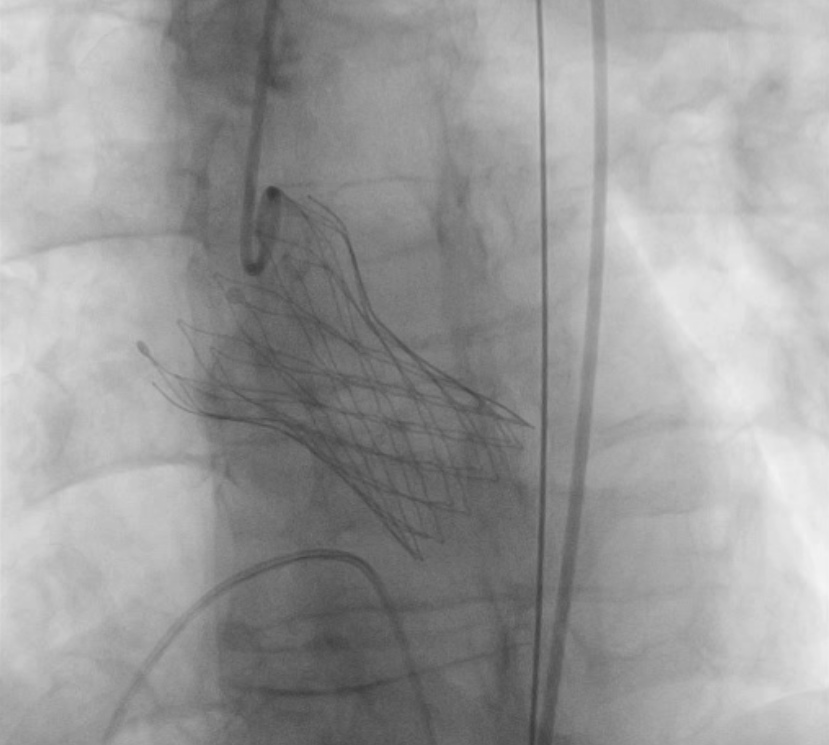

11月12日下午,楚天舒主任团队成功为患者进行了TAVR换瓣治疗,手术中通过导管测量得到植入前心室主动脉压力差大于90mmHg,提示主动脉瓣狭窄已严重阻碍心脏正常泵血工作。人工瓣膜成功植入后,可见人工瓣膜瓣叶开阖自如,心脏对外泵血压力明显减轻,导管测得压力阶差降至10mmHg以下,血流动力学即刻得到改善。这提示着患者的主动脉瓣狭窄情况,已较前大为缓解,手术圆满成功。术后患者生命体征平稳,带气管插管安全返回ICU特护。一天后,患者被转回心血管内科二病区继续治疗。在心血管内科二病区全体医务人员的精心治疗与护理下,患者于17日顺利出院。